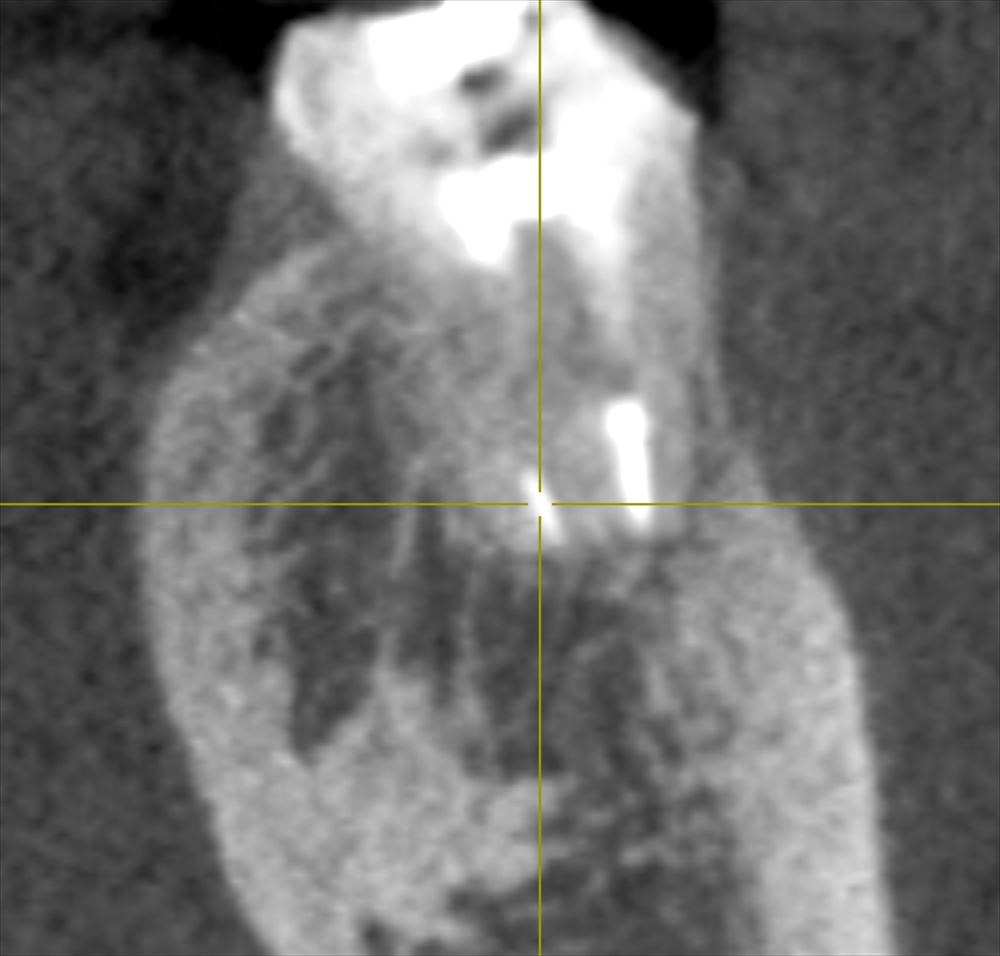

CTでも確認ML根 術前 ある。

術後 ない!!

これで次回は根管充填です。